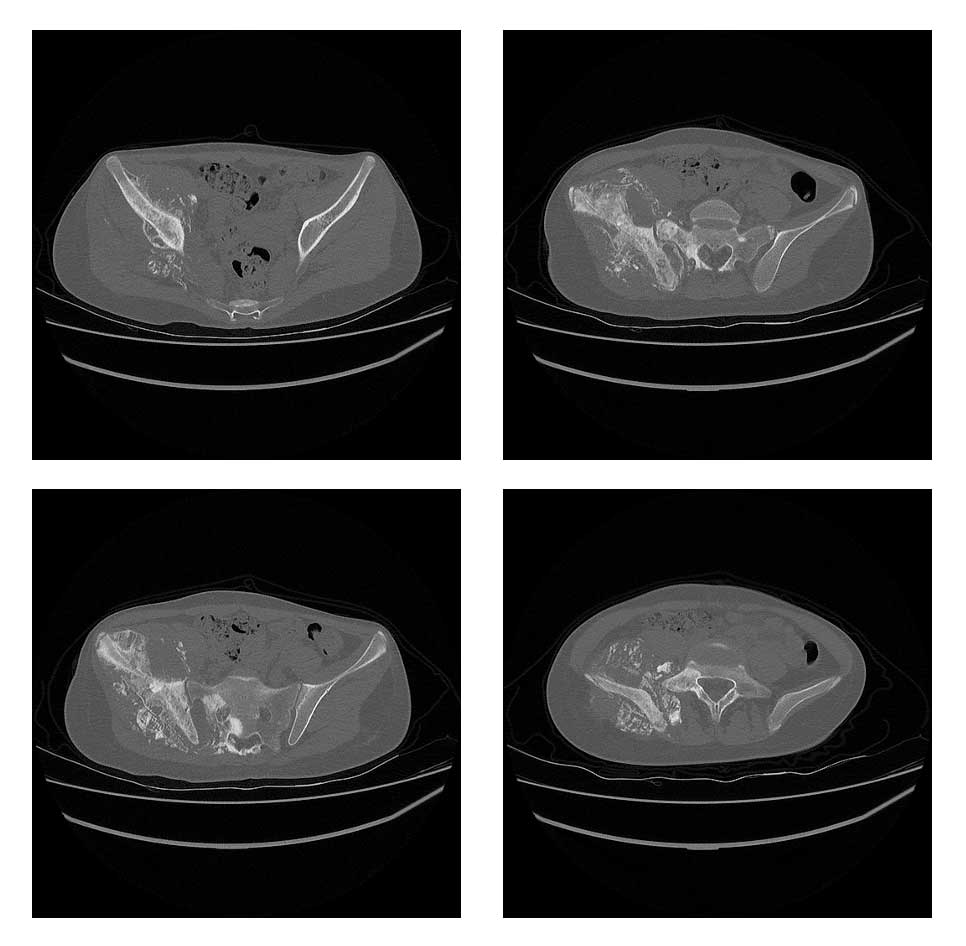

Ameliyat Öncesi: Tomografide lomber 4.vertebradan başlayıp sakrum ve iliak kanattan kalça eklemine kadar uzanan yumuşak dokuyu infiltre eden ve kemik harabiyetine neden olan düzensiz sınırlı tümör dokusu görülmekte.